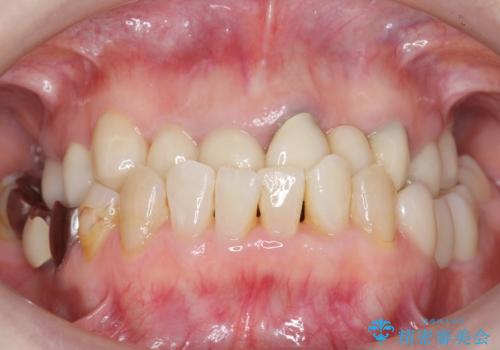

虫歯を丁寧に除去した後に歯根を分割し、骨を削合して健全歯質を露出させる骨外科手術を行いました。

手術後に根管治療を行い、歯肉と骨の治癒を十分に待った後ブリッジによる補綴治療を行いました。

ご希望通り歯を抜かずに残すことができ、喜んで頂けました。

セルフメンテナンスしやすいよう、ブリッジと歯ぐきの間に歯間ブラシを通すことができるように作製しています。